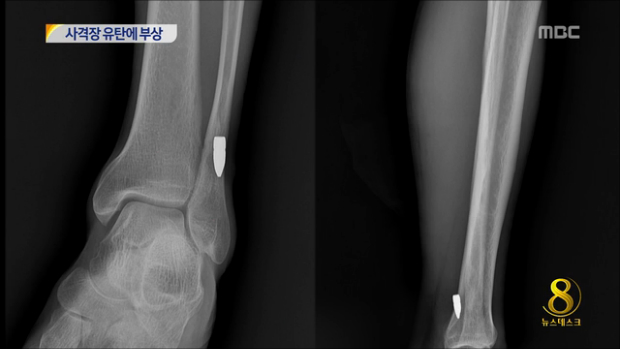

군 사격장 훈련 유탄에 민간인 '발목 부상'

◀ANC▶ 공사장에서 한창 일하던 남성이 어디선가 날아온 총알에 맞아 크게 다쳤습니다. 알고 보니 인근 사격장에서 훈련중에 날아온 총알이었습니다. 김미희 기자입니다. ◀VCR▶ 경기도 고양의 자동차 재활용센터 공사장. 어제 오전 느닷없이 총알 한발이 날아와 작업중이던 ...